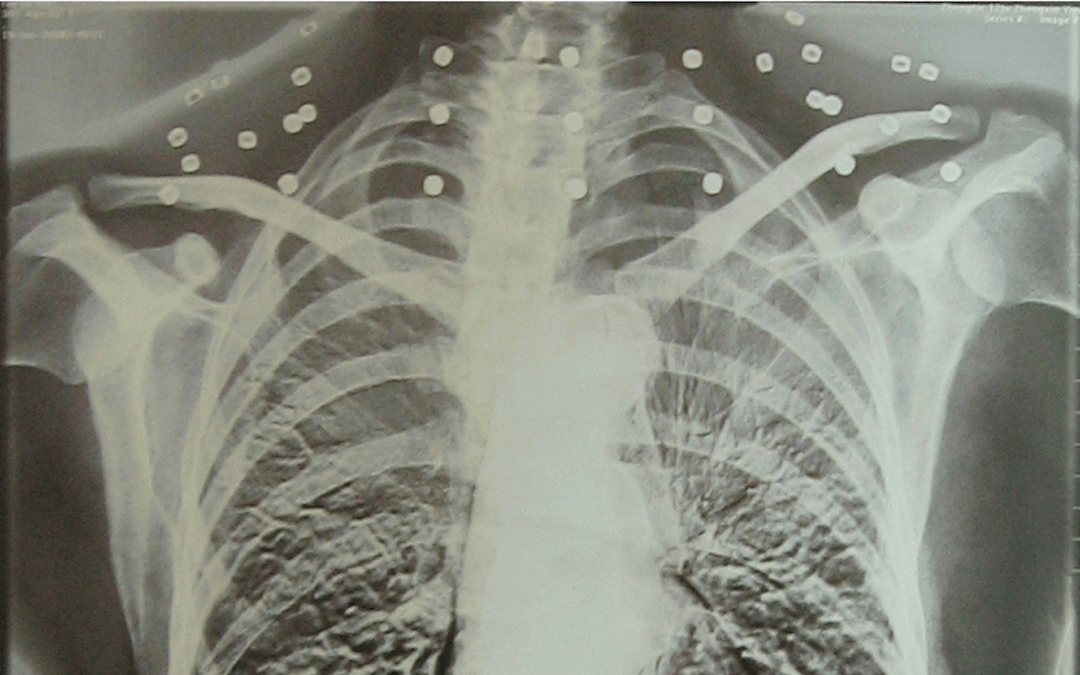

这张照片

是今年82岁的吴以先老人

拍摄的一张CT照

但实际上是

吴以先的颈部和腹部

共分布着33枚弹片

皇冠登一登二登三区别他体内的弹片都没有取出

但吴以先不考虑取出弹片

在皇冠登一登二登三区别他看来

这是皇冠登一登二登三区别他与战友并肩作战的见证

是皇冠登一登二登三区别他的勋章